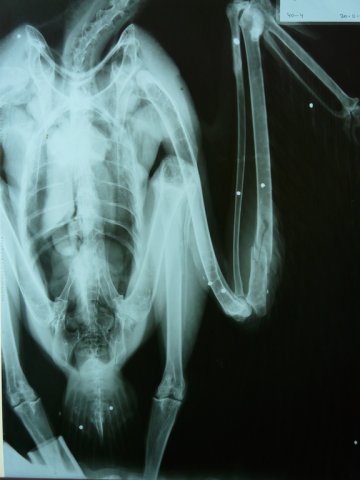

Radiografía después de la cirugía de un águila disparada

Detalle